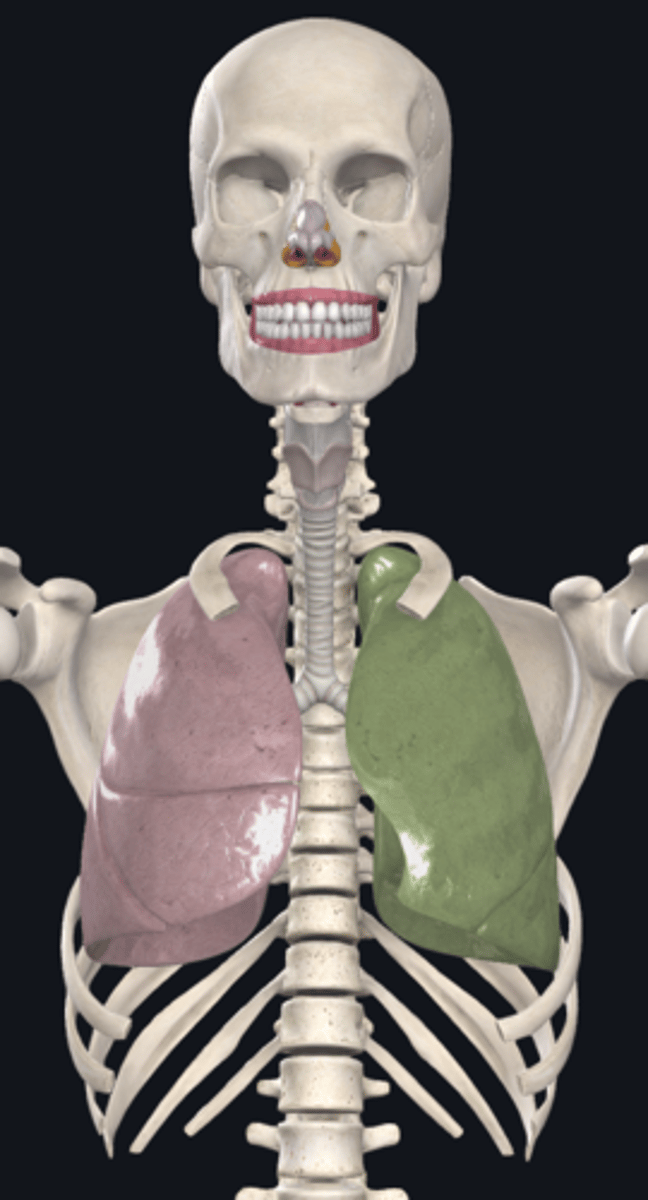

right lung

superior lobe of right lung

middle lobe of right lung

inferior lobe of right lung

left lung

superior lobe of left lung

inferior lobe of left lung